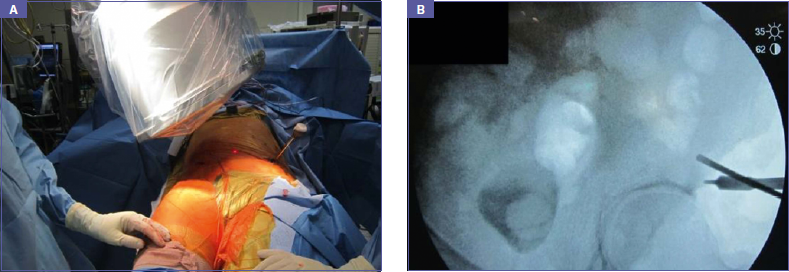

Unstable pelvic ring injuries are severely debilitating, lifethreatening injuries that require emergent or urgent intervention as part of trauma life support, damage control orthopedics 1. External fixation (Ex Fix) of a pelvis has many shortcomings, remaining a cornerstone for its utilization as an anterior pelvis external fixator for emergent temporary stabilization of a pelvic ring injury. Drawbacks on the other hand include pin site infections that affect 25-50% of patients, osteomyelitis affecting 7% of patients, loosening of the pins, loss of reduction in up to one third of patients, challenges associated with obese patients, particularly nursing and pin site care, limitations with mobilization and sitting up 1,6-12. Furthermore, any prone positioning for surgical approach to the spine is problematic. With the aim of improving patient comfort and minimizing the complications associated with an external fixator, the leading author Dr. R.Vaidya, popularized a technique using the established principles of anterior external fixation, but with internal implants 5. The technique consists of single supra acetabular pedicle screws placed in each ilium, connected with a subcutaneous titanium rod, which is described as an anterior subcutaneous pelvic internal fixator (ASPIF); it is designed to be used in conjunction with posterior pelvic stabilization to effectively manage a pelvic ring injury, without the shortcoming associated with an external fixator (Fig. 1A-B).

Figure 1A-B.Example of INFIX, with supra acetabular pedicle screws connected with a subcuta-neous titanium rod.